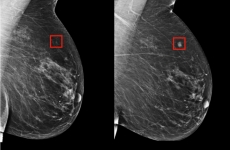

A Google AI system proved as good as expert radiologists at detecting which women had breast cancer based on screening mammograms and showed promise at reducing errors, researchers in the United States and Britain reported.